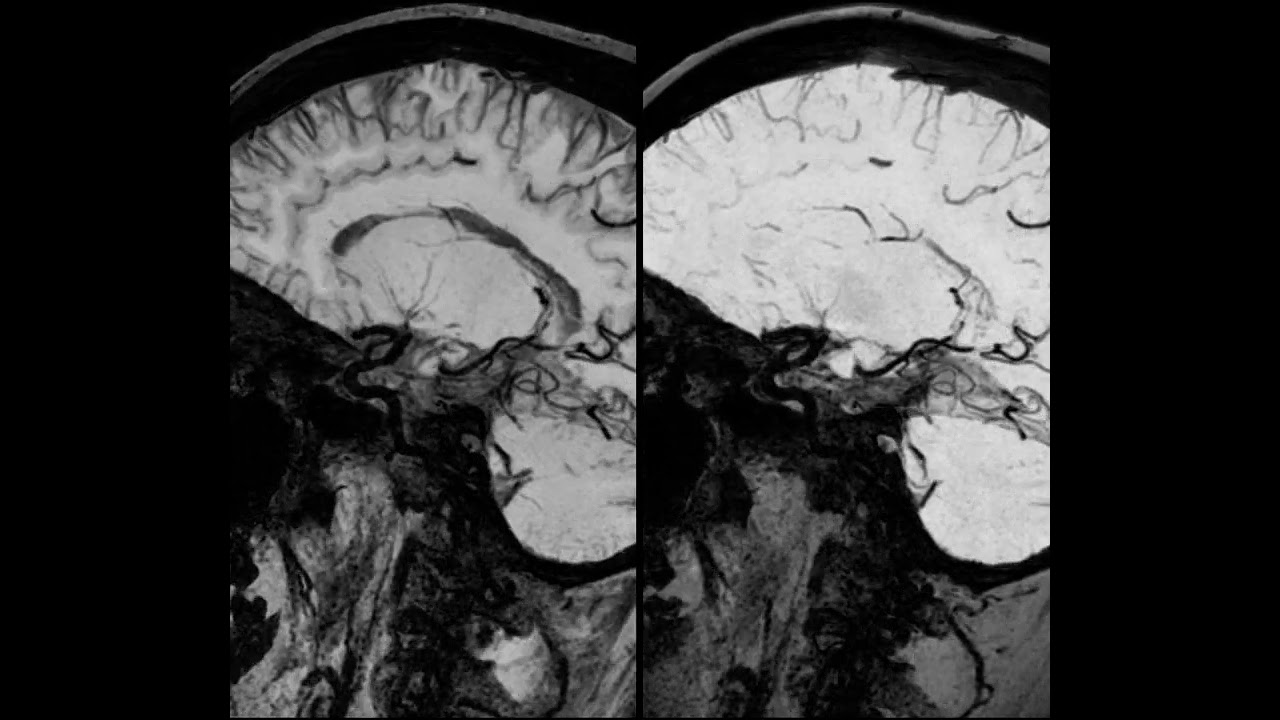

Vessel wall imaging using high resolution 3D CUBE T1 fat sat with MSDE and HyperSense

✳️ MSDE, a spin echo-based diffusion weighted option, is employed once per shot to suppress flow within the volume and is finalized with a tip-up pulse to return magnetization to the longitudinal axis (driven equilibrium).

✳️ MSDE is compatible with Cube sequences.

✳️ This technique effectively eliminates signal from flowing blood while preserving high signal in the surrounding stationary tissues, resulting in black blood appearance.